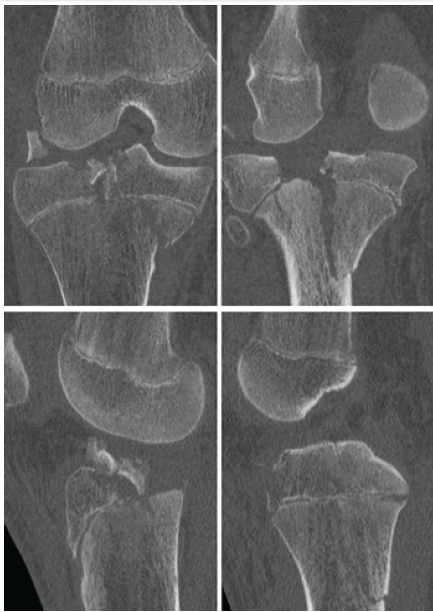

The patient was taken urgently to the operating room for closed reduction and application of an external fixator. A computed tomography (CT) scan was obtained after external fixation (Fig. 2); this demonstrated a Salter Harris type 4 pattern of the medial tibial condyle with widely displaced articular fragments of the lateral tibial plateau.

Figure 2: Select computed tomography scan cuts demonstrating Schatzker IV/Moore 2 tibial plateau fracture and large intra-articular fracture fragment.